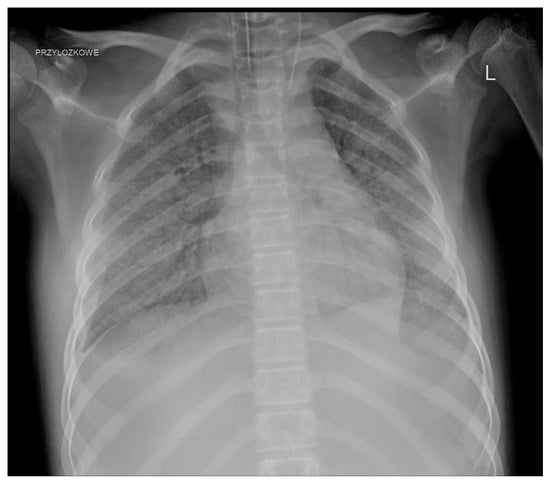

We observed a few complications related to GC administration. One patient developed an anaphylactic reaction during the second transfusion. One girl, who required hospitalisation in the ICU as a result of infection, about 2 h after the administration of the GC, developed shock symptoms with the deterioration of the general condition and circulatory and respiratory instability; transfusion-related acute lung injury (TRALI) was diagnosed after further investigation (Figure 3).

A non-negligible issue is the side effects. Initially, side effects, mainly from the respiratory system, led to the suspension of GC use [6]. The significant development of serological methods has significantly improved the safety of GC use. The most common adverse reactions are not markedly different and do not occur more frequently than during the transfusion of other blood products [6]. Some of them can be avoided by proper donor screening, appropriate pretransfusion premedication (such as antihistamines, acetaminophen, and steroids), and maintaining adequate intervals between the administration of other medications (e.g., amphotericin B) [17]. Gea-Banacloche summarised the most common toxicities, including fever, HLA sensitisation, pulmonary reactions, and CMV infection (if CMV-positive donors are used) [10]. Fever appears to be the most common complication. Alloimmunisation seems particularly problematic in the context of further anticancer treatment (in one patient, we struggled for a long time with the consequences of this complication). The risk of transfusion-transmitted infection is low as donors are routinely screened for infectious diseases, but it still exists [9]. Pulmonary complications, which are considered acute transfusion-related adverse events, appear to cause particular (and justified) concerns. Grigull et al. reported the need for the temporary escalation of respiratory support in patients undergoing mechanical ventilation, worsening of pulmonary symptoms in two children with viral pneumonia, and even the development of progressive respiratory failure during GC transfusion [18]. In a systematic review covering studies from 1966 to 2006 on granulocyte transfusions in neutropenic children, the authors observed pulmonary complications in only seven recipients, ranging from mild to more severe respiratory symptoms, but TRALI was not reported. They concluded that novel methods of leukapheresis have significantly reduced the risk of severe pulmonary complications that were observed in the past [19]. However, such reports still appear even in significantly more recent studies. Díaz et al. in a group of 13 patients with underlying acute infection observed respiratory symptoms in 6 patients (46%) including hypoxemia and tachypnea that were likely secondary to GC transfusions [34]. Weingarten et al. described one episode of life-threatening grade 4 dyspnoea (in a cohort of 21 patients) [28]. TRALI, which was diagnosed in one of our patients, remained in close association with GC administration.

Figure 3. TRALI after GC transfusion.